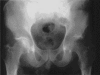

FIG. 1. Plain radiograph of transient osteoporosis of the left hip. Osteoporosis of the left femoral head and neck as well as periacetabular osteopenia can be seen. The right hip is normal.